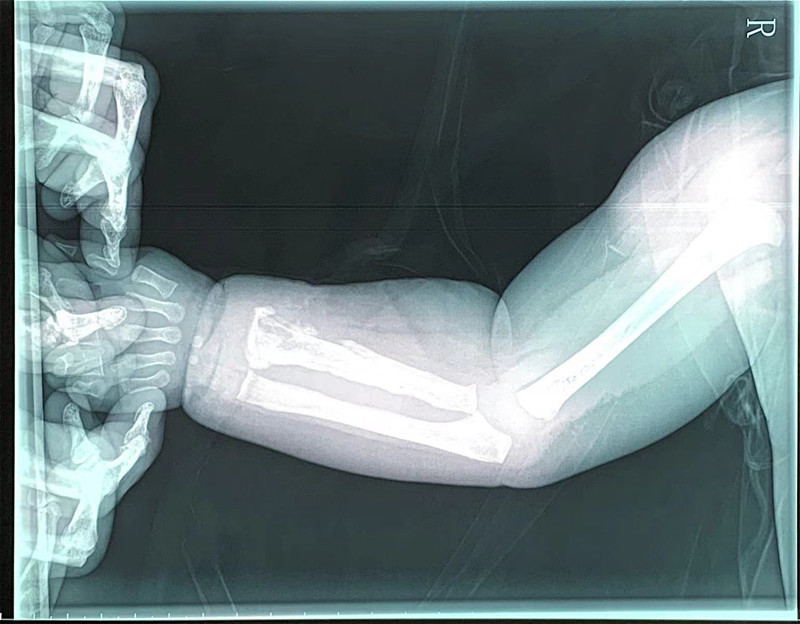

局部切开,减压、引流

小宇一周前发过烧,后来胳膊肿了。小宇妈妈说,原以为孩子只是普通感冒,打针后烧退了,但胳膊一直不见好转。这种情况,医生怀疑是急性骨髓炎。拍片显示,其桡骨骨质改变,结合核磁检查结果,医生综合分析,明确是急性骨髓炎。由于已错过发病初期48小时最佳治疗期,不能保守治疗,医生建议马上手术。随后,副主任医师高凤奇为小宇手术,局部切开、病灶清除、开窗减压、置管冲洗引流,术后又进行抗感染治疗。2周后,小宇症状改善,无肿痛、无化脓液,基本痊愈。